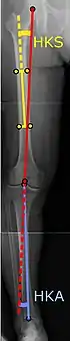

Angles commonly measured before knee replacement surgery: |

To indicate knee replacement in case of osteoarthritis, its radiographic classification and severity of symptoms both should be substantial. Such radiography should consist of weightbearing X-rays of both knees: AP, lateral, and 30 degrees of flexion. AP and lateral views may not show joint space narrowing, but the 30-degree flexion view is most sensitive for narrowing. Full-length projections also are used in order to adjust the prosthesis to provide a neutral angle for the distal lower extremity. Two angles used for this purpose are:

- Hip-knee-shaft angle (HKS),[9] an angle formed between a line through the longitudinal axis of the femoral shaft and its mechanical axis, which is a line from the center of the femoral head to the intercondylar notch of the distal femur.[11]

- Hip-knee-ankle angle (HKA),[10] which is an angle between the femoral mechanical axis and the center of the ankle joint.[11] It is normally between 1.0° and 1.5° of varus in adults.[12]